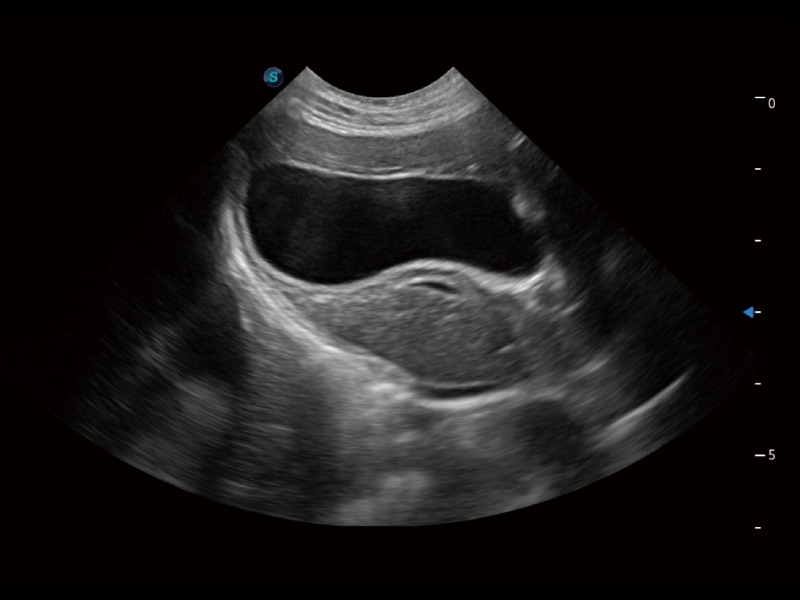

• Auto Bladder 膀胱自动测量

一键自动识别膀胱壁及自动测量膀胱容积,不受膀胱形状和大小的限制,帮助医生快速精准获得测量的数据。

优异的基础图像

ProPet 70 全新的动物超声智能软件和丰富的探头群,为动物医生提供了高清晰度和精细分辨率的图像,无论在宠物、马科、畜牧还是实验室动物等应用中都可以轻松应对,为您的日常工作带来满意的体验。

(猫)胆囊

(犬)肝脏